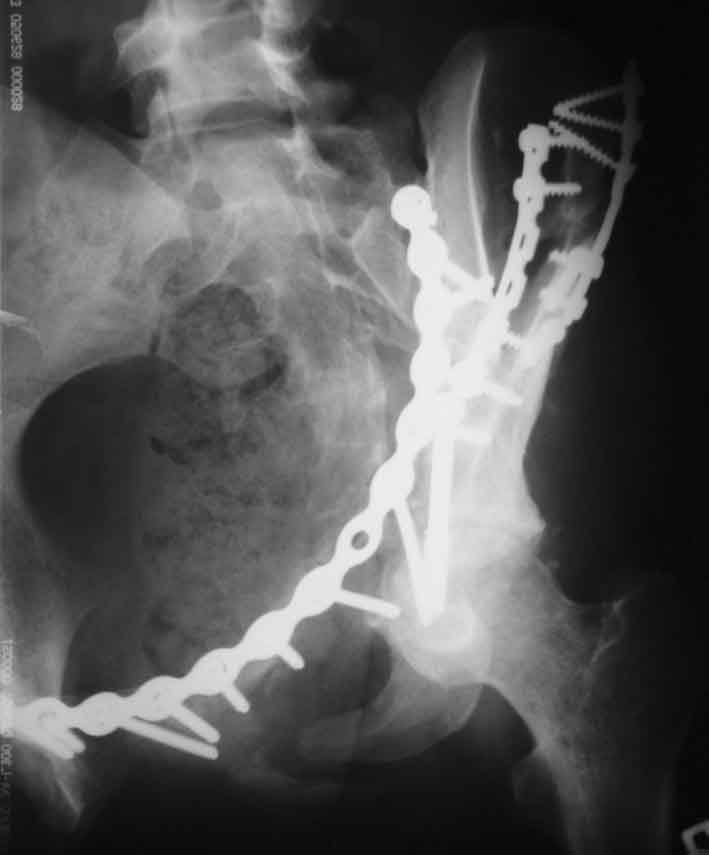

Рентгенограммы после операции

запирательная

A>РО - картина не очень, есть видимость винтов во впадине

По всей видимости, вы имеете в виду канюлированный винт, который проецируется на вертлужной впадине. Та вот, он проведен не через лонную, а седалищную кость. Вертлужная впадина абсолютно интактна. Это хорошо видно на проекции inlet.